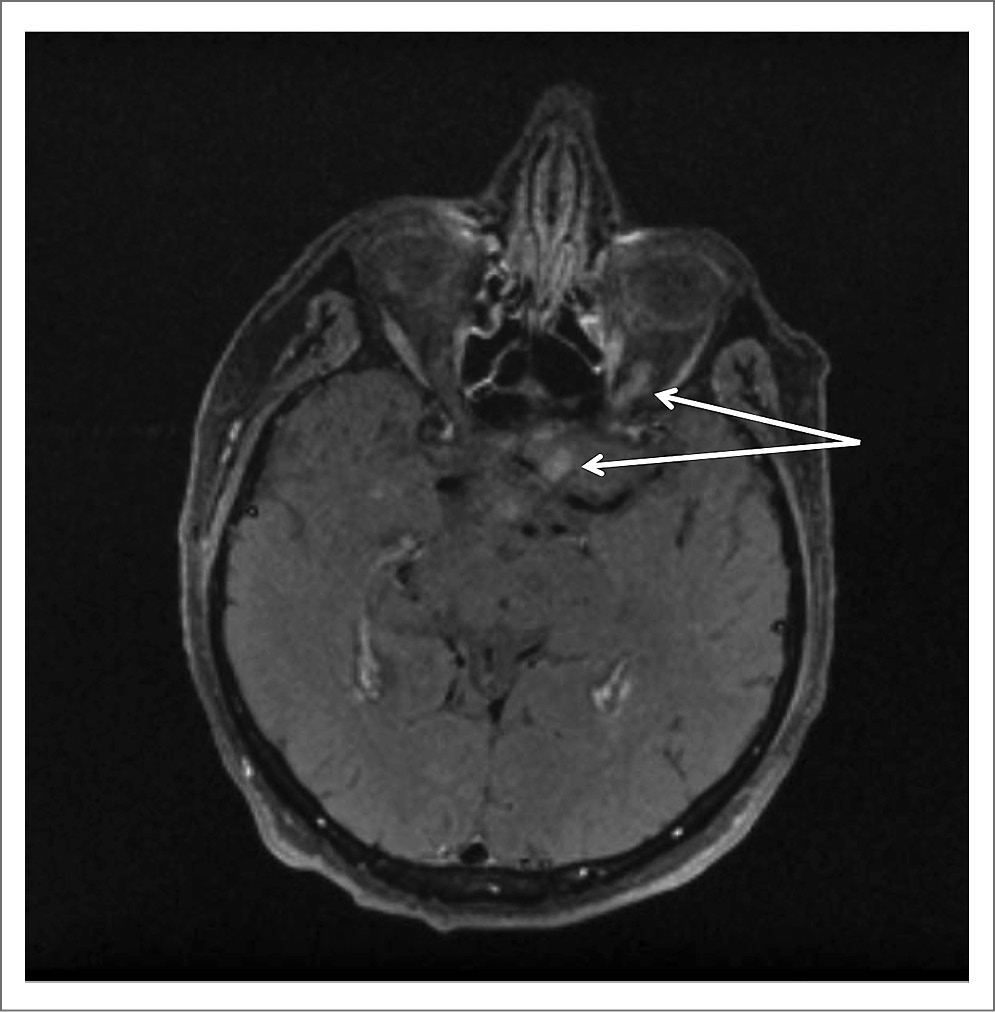

Для уточнения диагноза провели МРТ ГМ и спинного мозга. При исследовании ГМ отмечены единичные мелкие очаги в белом веществе и небольшие зоны лейкоареоза, отражающие микроангиопатию. МРТ-исследование спинного мозга в режимах T2-взвешенного изображения и FLAIR выявило протяженные участки повышенного МР-сигнала (на уровне шести шейных позвонков), заметное утолщение и неоднородную структуру шейного отдела спинного мозга, вероятно, воспалительного генеза (рис. 1, 2). При внутривенном контрастном усилении определялось накопление контрастного вещества в левом зрительном нерве на всем его протяжении (рис. 3) и в белом веществе спинного мозга, преимущественно в области задних столбов с переходом на нижнезадние отделы продолговатого мозга – зона аrea postrema (рис. 4).

Рис. 3. Накопление контрастного вещества в левом зрительном нерве (показано стрелками).

Оптический неврит при ОНМ может быть как с выраженным и стойким нарушением зрения [10], так и асимптомным, патология которого выявляется только специальными методами исследования [1]. У нашего пациента расстройства зрения были выраженными без каких-либо характерных изменений при офтальмоскопии, и только МРТ с контрастированием позволило остановиться на воспалительном характере поражения зрительного нерва (рис. 3).